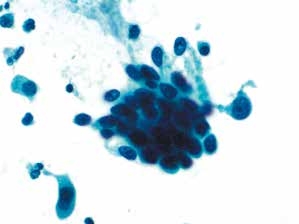

图4-31 高度鳞状上皮内病变(HSIL)(高倍、液基、巴氏染色)

异型增生的细胞密集成团,胞核明显增大,核膜不规则,核质比明显增高。

图4-32 高度鳞状上皮内病变(HSIL)(高倍、液基、巴氏染色)

细胞核异型性明显,染色质粗颗粒状,核膜不规则,胞质浓染,核质比高。此为异型性明显的不成熟化生细胞,判读为HSIL。